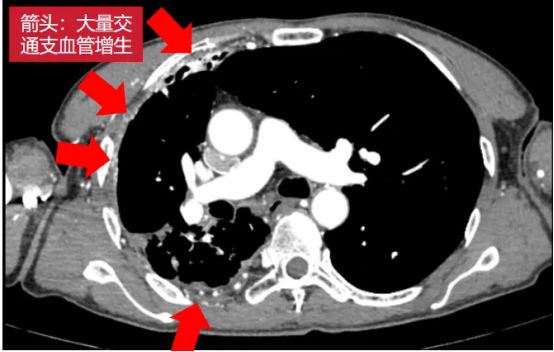

术前影像(左右滑动查看更多)

该患者为61岁男性,肺部病情错综复杂。4年前确诊肺结核后因治疗不规范,发展为“利福平耐药”结核,病情持续恶化。2年来反复咯血,虽经3次支气管动脉栓塞术暂时控制,但病灶顽固,收治入院时已形成多重诊断:毁损肺(右上)、右肺下叶鳞癌(背段)、肺曲霉菌病、陈旧性肺结核。其右肺上叶完全丧失功能,并与胸壁形成致密粘连,医学上称为“毁损肺”——胸外科领域公认的极高难度手术。

手术如期进行,然而打开胸腔的瞬间,其严峻程度远超预期:胸腔呈广泛致密黏连、完全闭锁,右肺上叶仿佛被水泥浇筑在胸壁上;肺表面及壁层胸膜布满大量脆弱的新生血管,呈现出“碰一下就出血”的凶险局面。